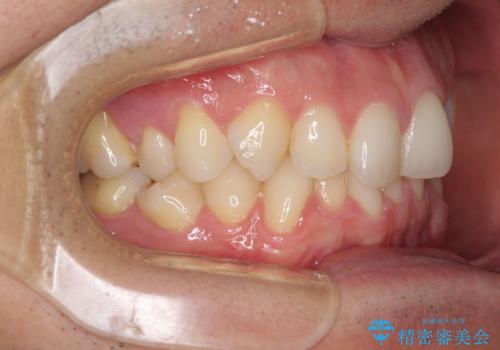

ディープバイトと叢生 インビザラインによる矯正治療

- 前歯のディープバイトと叢生を気にして来院された患者様です。

目立ちにくい装置を希望されていたため、ワイヤー装置とインビザラインを提案したところ、インビザラインを希望されました。

上下ともに叢生が認められたため、親知らずすべてを抜歯し、歯列全体を後方へ移動させることで歯列を整えることとしました。

上顎奥歯の銀歯も気になっていたので、矯正治療の途中でセラミッククラウンへ変更し、その後歯列を仕上げていくこととしました。

ディープバイトもデコボコも改善され、気になっていた銀歯もセラミックとなり、患者様には大変満足していただきました。